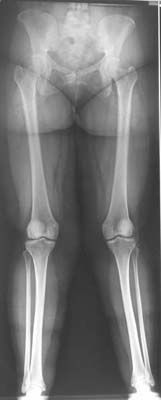

Technique Ostéotomie fémorale distale de varisation par soustraction interne. , Jean-Louis Doré Tours, France 🖂 cjl.dore@wanadoo.fr , Jean-Michel Frieh Centre Hospitalier Départemental - 85925 La Roche sur Yon, France 🖂 jmfrieh@wanadoo.fr N°168 - Novembre 2007 ● 18 min de lecture